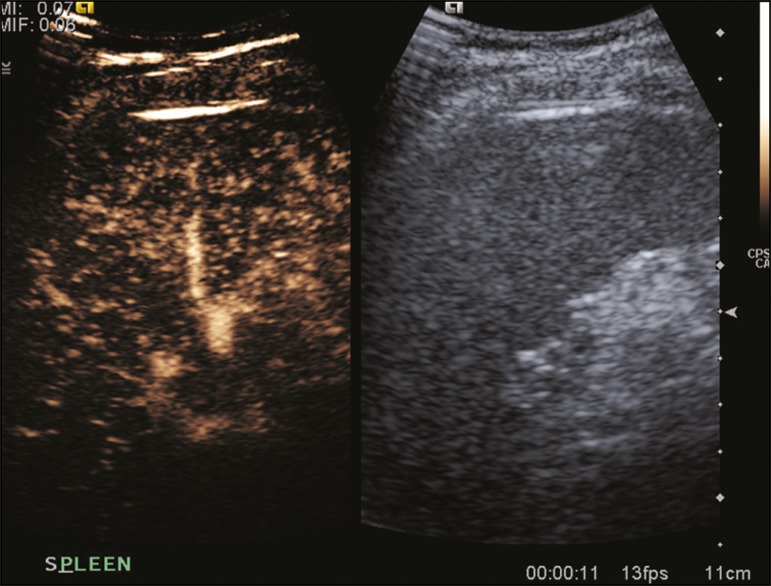

Common and uncommon features of focal splenic lesions on contrast-enhanced ultrasound: a pictorial review

A caracterização de lesões focais esplênicas pela ultrassonografia pode ser bastante desafiadora. A introdução da ultrassonografia com contraste por microbolhas vem ganhando papel importante no campo da avaliação por imagem das doenças esplênicas, oferecendo um método livre de radiação ionizante. Após a implementação da ultrassonografia contrastada na prática médica, doenças malignas como linfomas e metástases, […]